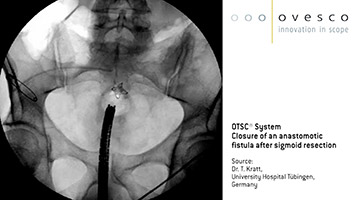

Behandlung einer Fistel an der Anastomose nach laparoskopischer Sigma-Resektion